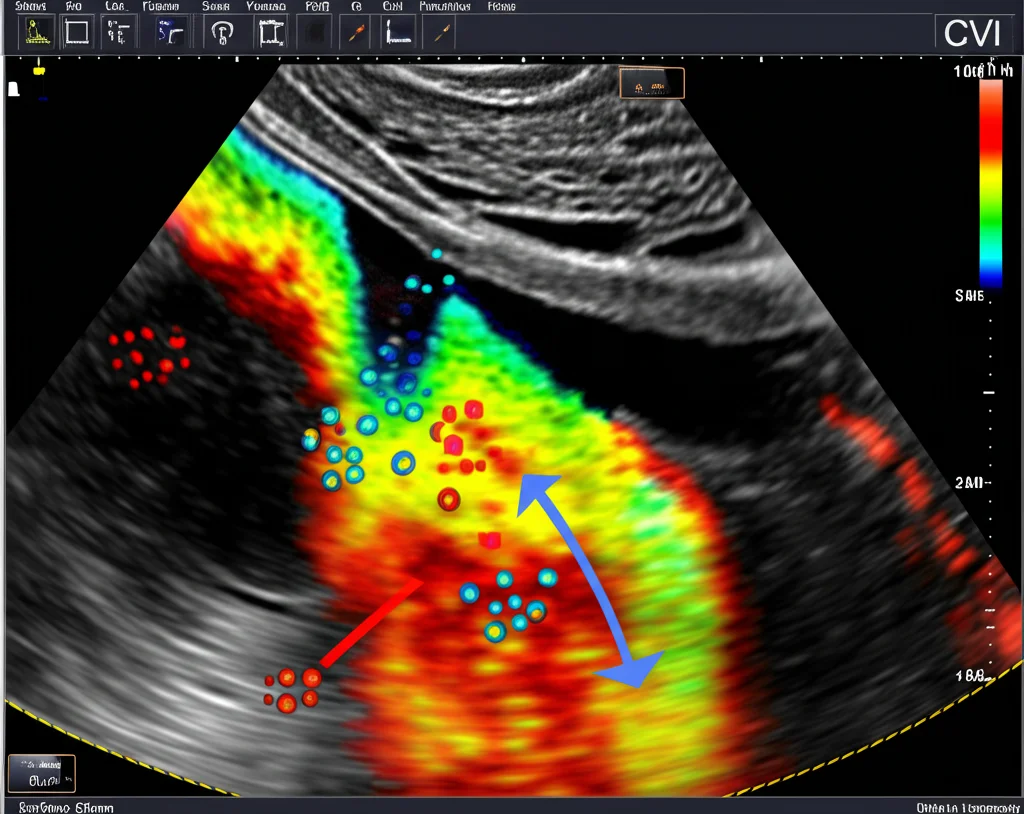

Qui le cose si fanno davvero interessanti. L’HFR CEUS è potente, ma l’interpretazione delle immagini può ancora avere un margine di soggettività. Ed ecco che arriva il CVI (Contrast Vector Imaging). Immaginatelo come un software super intelligente che lavora “dietro le quinte” sulle immagini HFR CEUS. Il CVI è una tecnica di post-processing che fa due cose fantastiche:

- Traccia automaticamente le microbolle: Segue il percorso di ogni singola microbolla all’interno del linfonodo.

- Visualizza il movimento: Mostra i risultati in vari modi, ad esempio con frecce colorate che indicano la direzione e la velocità del flusso sanguigno.

In pratica, il CVI ci dà una mappa dinamica e oggettiva di come il sangue si muove nel linfonodo, con una risoluzione spaziale e temporale pazzesca. Questo compensa alcune delle limitazioni della CEUS tradizionale e ci aiuta a interpretare i pattern di flusso in modo più accurato.

Quando CVI Fa la Differenza

La cosa notevole è che il CVI ha aiutato a “correggere” l’interpretazione in alcuni casi dubbi. Nello studio, c’erano linfonodi che all’HFR CEUS sembravano avere un pattern ibrido o addirittura centrifugo, ma l’analisi CVI, tracciando le bolle, ha rivelato un chiaro pattern centripeto, tipico della malignità. E la biopsia ha confermato che il CVI ci aveva visto giusto! Questo dimostra il valore aggiunto del CVI: rende visibile e oggettivo ciò che all’occhio umano, anche esperto, può sfuggire, specialmente nei linfonodi piccoli o con flusso molto rapido. La concordanza con i risultati patologici è migliorata significativamente passando da un valore kappa di 0.66 (HFR CEUS da sola) a 0.81 (HFR CEUS + CVI). Un bel salto di qualità!